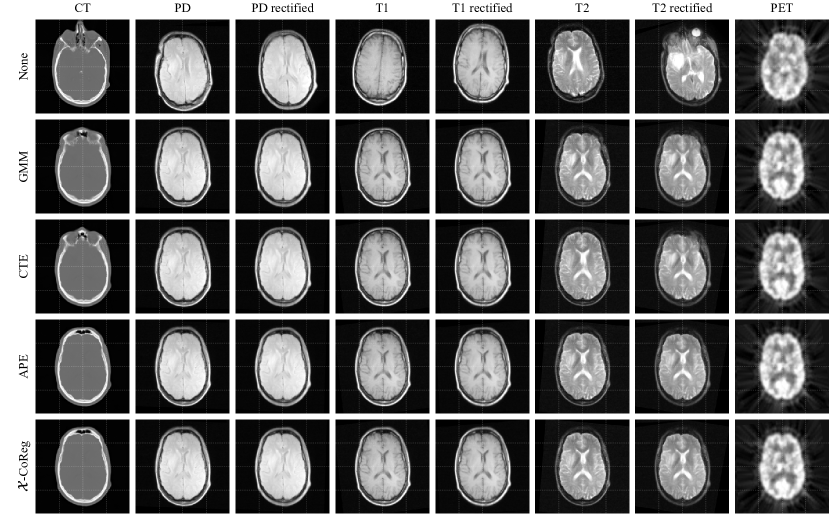

Multimodal groupwise registration. Joint analysis of images from multiple acquisitions requires groupwise registration to a common coordinate space, where complementary information of the corresponded anatomies can be collected [13]. To perform a proof of concept for multimodal groupwise registration, we validated the proposed method on the BrainWeb and RIRE datasets. The two experiments were aimed at testing the effectiveness of the 𝒳𝒳\mathcal{X}-metric on images from various modalities and organs, as well as the situations where registration was performed with different transformation models, i.e. nonrigid or rigid. The results were compared to previously discussed groupwise similarity metrics, including the conditional template entropy (CTE) [6], the accumulated pairwise estimates (APE) [4], and the Gaussian mixture model (GMM) [16].

Registration methods. The groupwise registration methods for comparison include:

• 𝒳𝒳\mathcal{X}-Reg-UN. This approach uses the proposed 𝒳𝒳\mathcal{X}-metric in Eq. 8 and the procedure in Algorithm 1. As no prior knowledge of the appearance model is required for the proposed algorithm, it is tagged as ”UNsupervised”.

• CTE. This method uses the conditional template entropy proposed in [6] as the groupwise similarity metric. Unlike our method that computes an anatomical template as 𝚪𝚪\bm{\Gamma}, it assumes a grey-valued template estimated by principal component analysis (PCA) from the warped images.

• APE. This method uses the accumulated pairwise estimates proposed in [4], computed as the sum of all pairwise mutual information from the warped images. Thus, it has a heavy computational burden.

• GMM. This method uses the MLE from a Gaussian mixture model to achieve co-registration [16]. Instead of a factorized categorical distribution assumed in our modelling, the GMM method presumes a multivariate Gaussian intensity distribution given the common anatomy. Note that GMM has the complexity of 𝒪(N3)𝒪superscript𝑁3\mathcal{O}(N^{3}) in general.

We also emphasize that the congealing (CG) algorithm is not applicable to this experiment, as a small image group (N=3𝑁3N=3) prevents accurate density estimation. Besides, for similarity metrics with kernel density estimators, we set the number of intensity levels as L=64𝐿64L=64 and the sample rate as 0.1. Moreover, four common anatomical structures were assumed for 𝒳𝒳\mathcal{X}-CoReg and GMM, i.e. K=4𝐾4K=4.